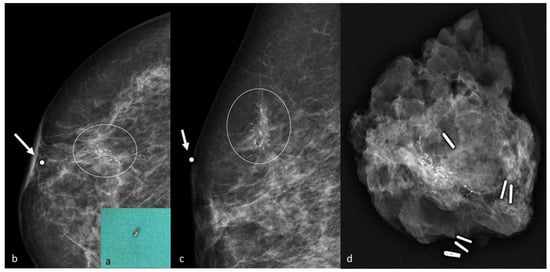

3. Carbon Marking